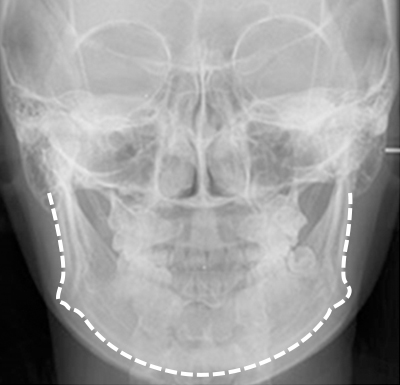

透過3D CT更精確分析,選擇適合每個人的矯正方法

採用最尖端的3D CT檢測,精確分析測量骨骼

· 引進快速掃描低輻射的Green16型裝置

· 三維立體式診斷3D CT裝置

· 骨骼精準診斷的面部輪廓矯正